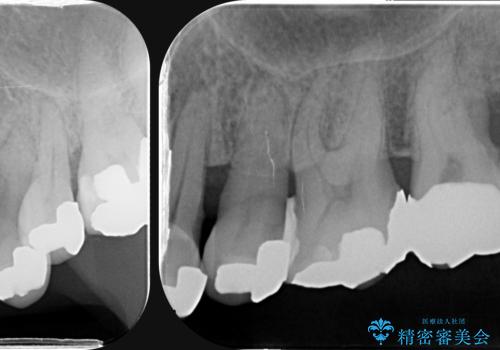

- 全体的に歯が揺れ、このままでは全て歯を失うのではないかと怖くなり歯周病治療を希望され来院されました。

歯列不正による第一小臼歯の骨吸収が認められ、機能咬合力の回復、大きな側方力に連結することで抵抗することのできるブリッジ補綴を選択しました。

歯周病による深いポケット・大きな側方力・短い臨床歯根・欠損の補綴、これらの問題を解決するために歯周補綴を兼ねたブリッジを選択しました。